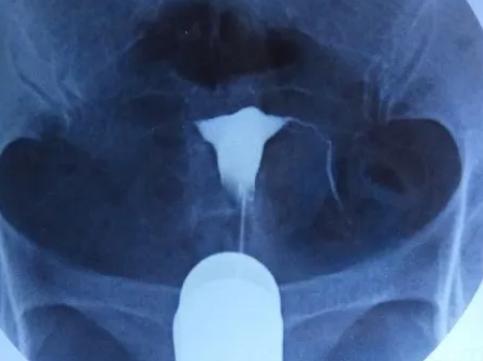

输卵管造影是一种通过检查输卵管来评估生育能力的常用检查项目,其中可以查看输卵管的形态和状态,以及输卵管内是否有积液。在输卵管造影时,许多人都想知道是否需要住院?

输卵管造影还可以用于诊断输卵管疾病,如输卵管积液,输卵管炎症,输卵管结石等,如果在造影检查中发现了这些病症,而且患者情况严重,那么可能会需要住院治疗。